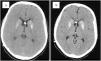

ResultsThe median age at first shunt was two months (0–67). The mean number of shunt revisions before inclusion was three. Shunt removal was attempted in seven patients without success; temporary success was observed in two patients who underwent ETV. Two patients had previous cranial expansions. The mean age at inclusion was 9.1 years (2.7–15.2). After the shunt system was exchanged and upgraded, clinical improvement was observed in 94.4% (17/18) of patients, and radiological improvement was observed in 83.3% (15/18) of patients. The median follow-up was 21 months.